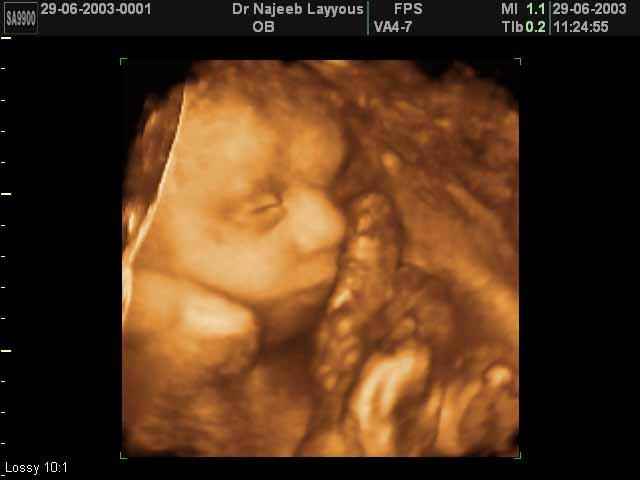

- صور لوجه الجنين في داخل الرحم

صور جانبية لرأس الجنين بجهاز الالتراساوند ثلاثي الأبعاد | الدكتور نجيب ليوس